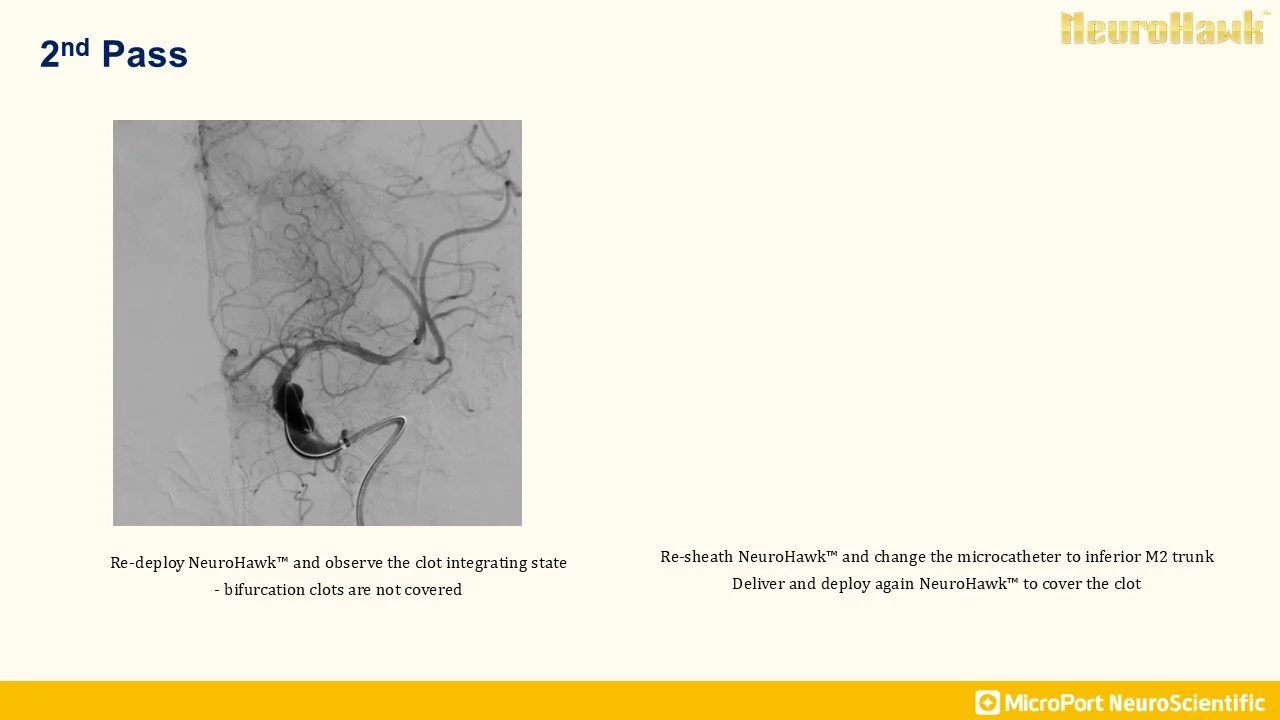

NeuroHawk Case 7